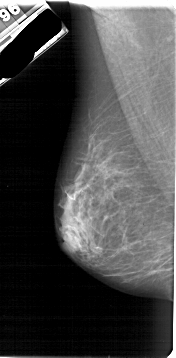

A_1791_1.RIGHT_MLO

RIGHT_MLO LINES 5311 PIXELS_PER_LINE 2611 BITS_PER_PIXEL 12 RESOLUTION 43.5 OVERLAY